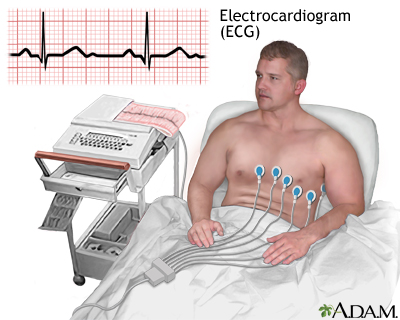

CSN Hospital (A unit of CSN Transparency Private Limited), was established in 2021 and in such a short span of time, it became one of the most respected hospitals in the State, and is also amongst the most preferred destinations for patients from several parts of the State. Our hospital specializes in cutting-edge medical procedures, spearheaded by experienced doctors who are skillfully supported by dedicated patient-care personnel.

Combining the best specialists and equipment to provide you nothing short of the best in healthcare

- Advanced medical equipments